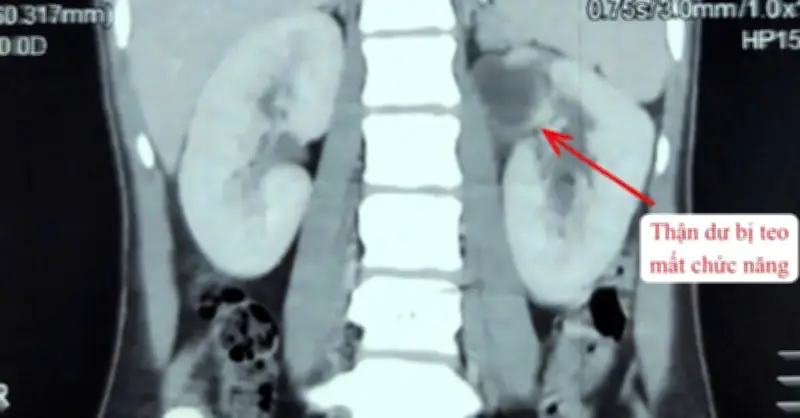

Câu chuyện bắt đầu khi cô gái này tham gia một đợt kiểm tra sức khỏe định kỳ. Qua các xét nghiệm hình ảnh như siêu âm và chụp cắt lớp vi tính, các bác sĩ đã vô cùng bất ngờ khi nhận thấy cô không chỉ có hai quả thận như người bình thường mà thay vào đó là ba quả thận hoàn chỉnh. Điều đáng chú ý là tình trạng này không gây ra bất kỳ triệu chứng hay vấn đề sức khỏe nào cho cô, và cô hoàn toàn không hay biết về sự tồn tại của quả thận thứ ba cho đến thời điểm đó.

Trong trường hợp của cô gái này, quả thận thứ ba được báo cáo là có kích thước và chức năng bình thường, không gây cản trở đến hoạt động của hai quả thận còn lại.